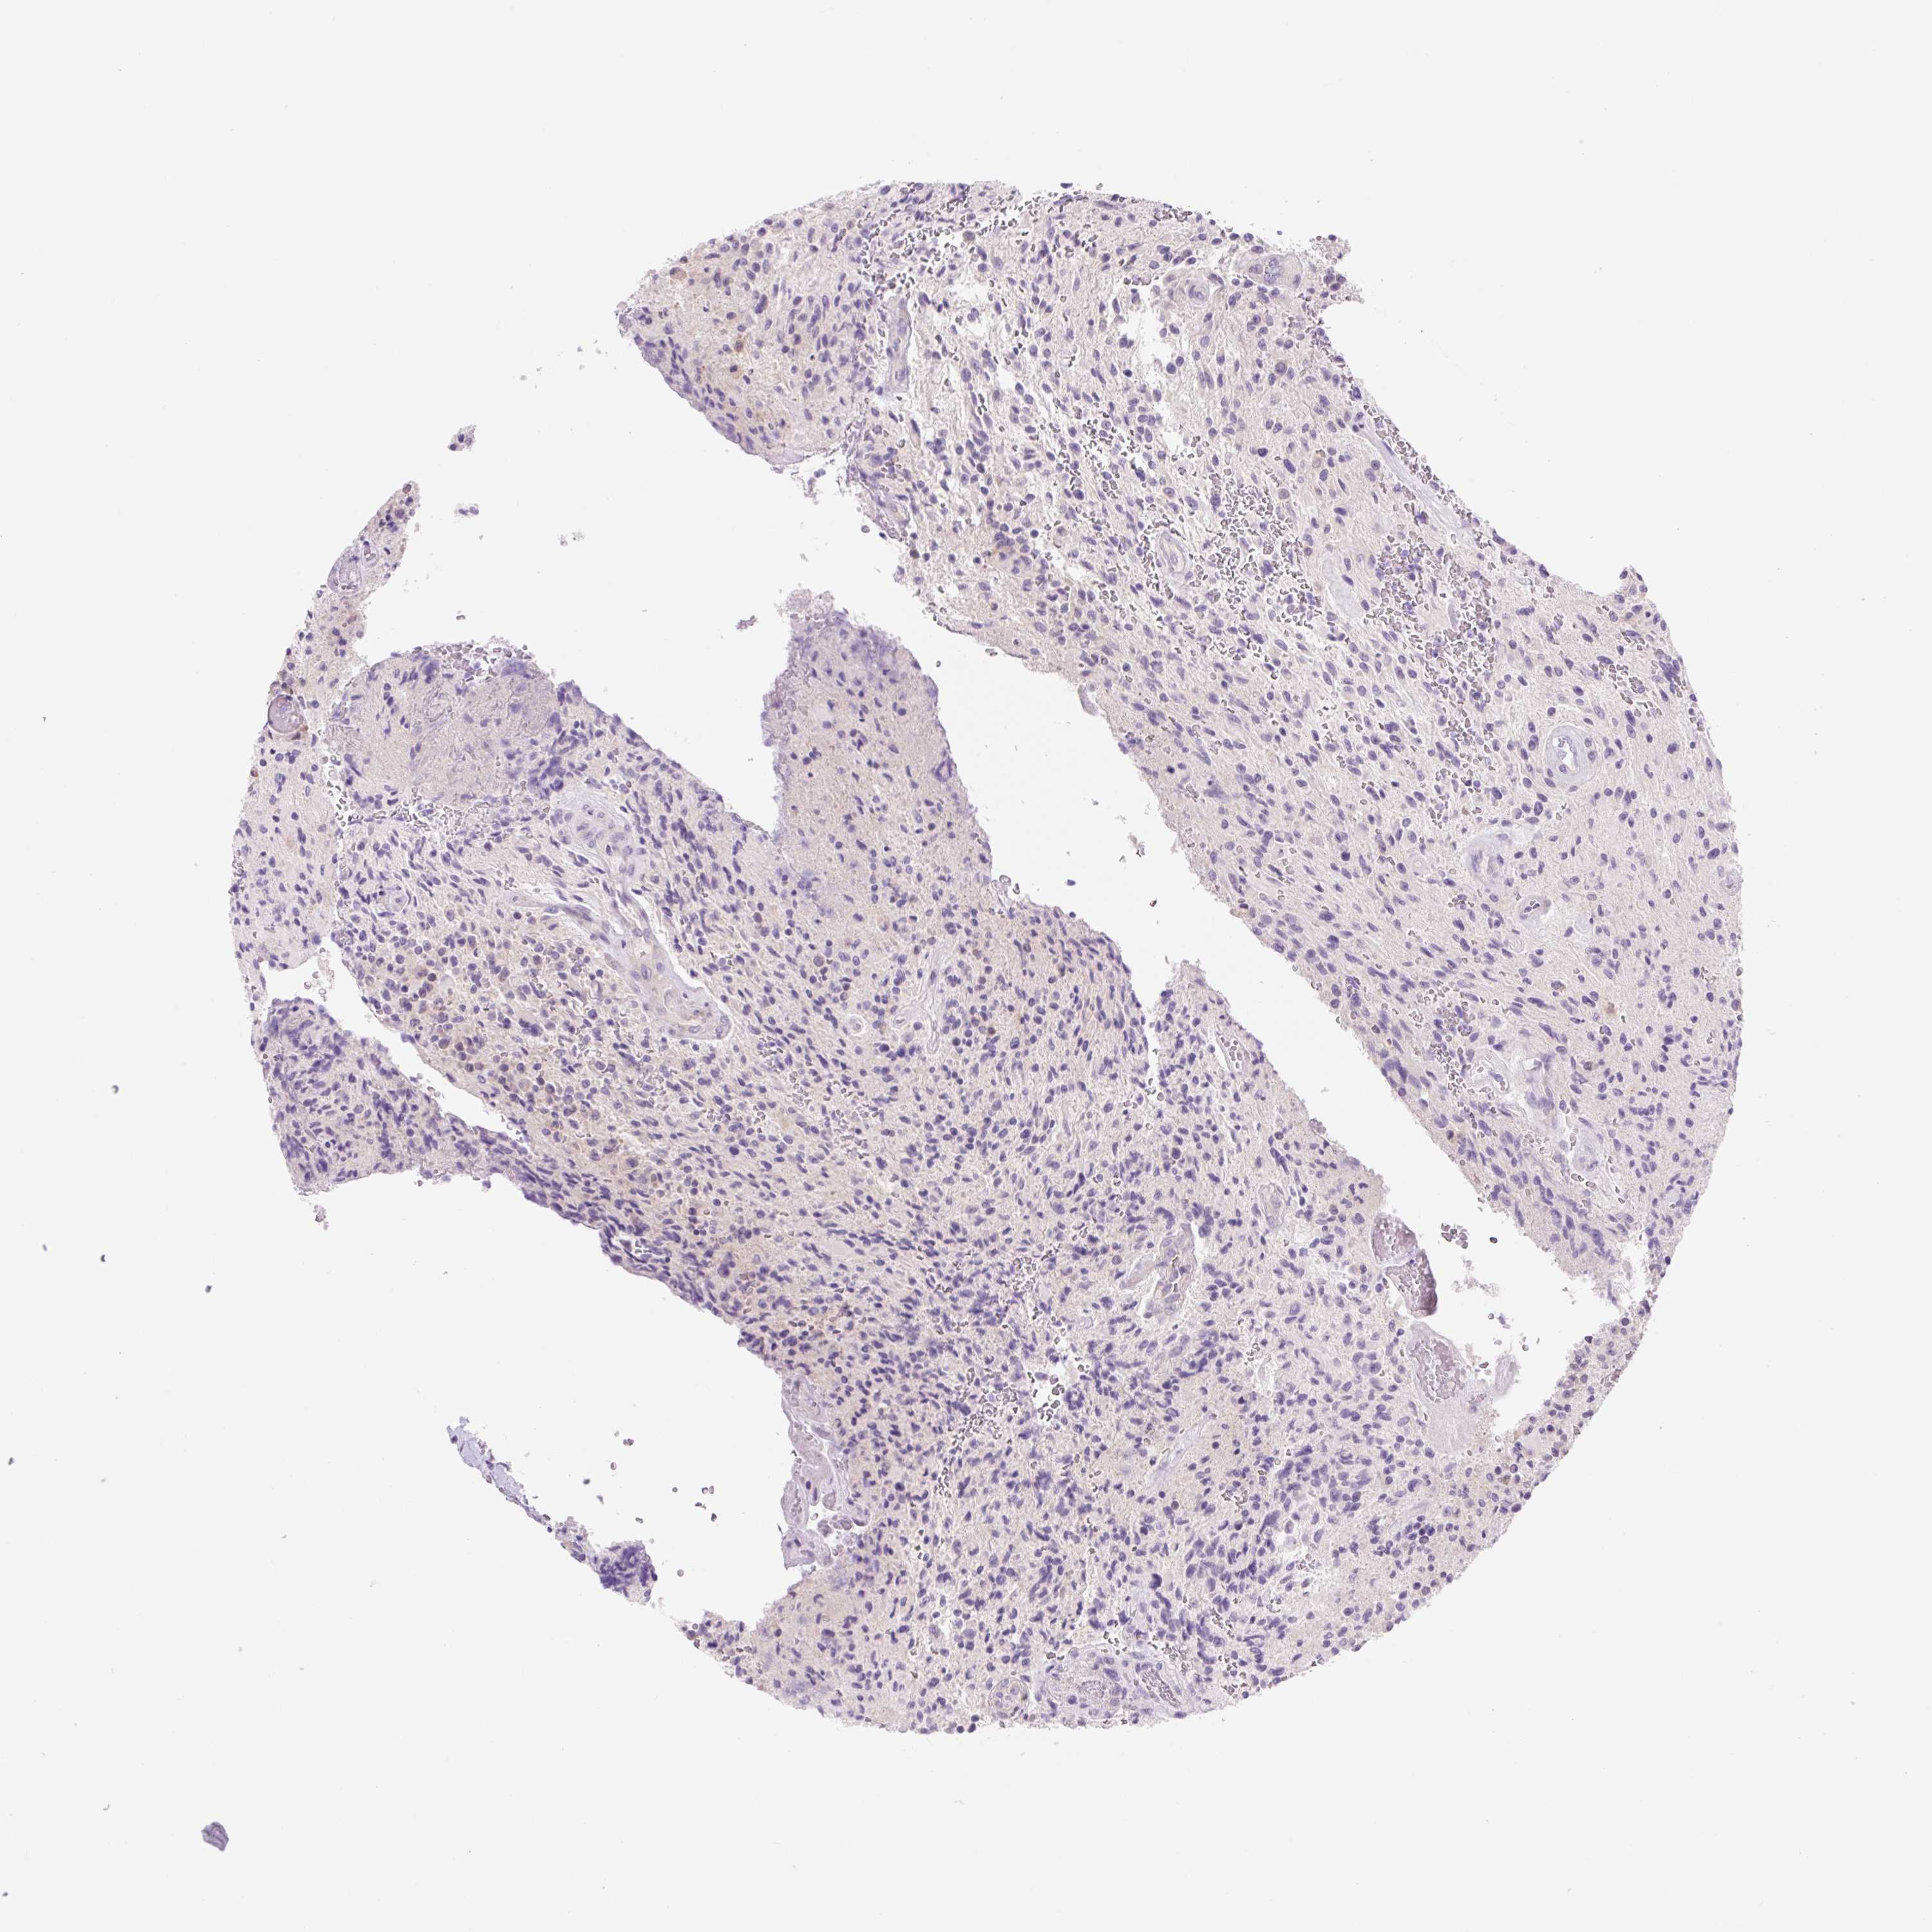

GLIOMA - Protein expressioni

A mouse-over function shows sample information and annotation data. Click on an image to view it in a full screen mode. Samples can be filtered based on level of antibody staining by selecting one or several of the following categories: high, medium, low and not detected. The assay and annotation is described here.

Note that samples used for immunohistochemistry by the Human Protein Atlas do not correspond to samples in the TCGA dataset.

Antibody stainingi

Antibody staining in the annotated cell types in the current human tissue is reported as not detected, low, medium, or high, based on conventional immunohistochemistry profiling in selected tissues. This score is based on the combination of the staining intensity and fraction of stained cells.

Each image is clickable and will lead to virtual microscopy that enables deeper exploration of all samples and also displays staining intensity scores, fraction scores and subcellular localization as well as patient and tissue information for each sample.

Antibody HPA046985

Antibody HPA053526

Staining

High

Medium

Low

Not detected

Intensity

Strong

Moderate

Weak

Negative

Quantity

>75%

75%-25%

<25%

None

Location

Nuclear

Cytoplasmic/membranous

Cytoplasmic/membranous,nuclear

Glioma, malignant, High grade

Glioma, malignant, Low grade